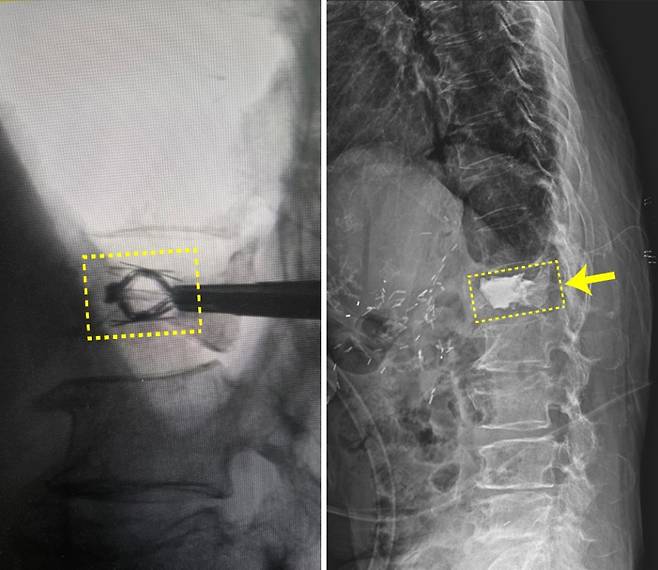

![임플란트를 삽입해 압박골절된 척추체를 들어올린 모습(사진 왼쪽)과 골시멘트가 채워진 모습(사진 오른쪽) [힘찬병원 제공]](https://img3.daumcdn.net/thumb/R658x0.q70/?fname=https://t1.daumcdn.net/news/202506/14/newsy/20250614060248558ifpf.jpg)

또 허리나 목이 아파 움직임이 어려운 경우에도, 금속 나사, 플레이트, 인공디스크 등을 삽입해 척추를 안정적으로 고정하거나 원활한 움직임을 돕기도 합니다.